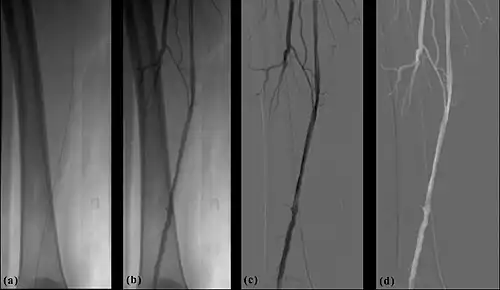

- The temporal-averaging feature of digital noise reduction can also be used for image presentation purposes so that the time course of the movement of contrast medium during a study can be displayed using just one image - see an example in Figure 7.4 from the peripheral study shown above - instead of a sequence of numerous images. Such an image is sometimes referred to as a Vascular Trace.

- Additional processes involve Bolus Chasing, Rotational Angiography and Volume Tomographic Angiography. Bolus Chasing[28] has been found to be particularly helpful in peripheral angiography, for example. Here, the progress of the contrast medium is tracked automatically and used to increment the table and/or XRT/image receptor movement to the next anatomical region. The subsequent set of subtraction images can then be used to construct a composite image of the peripheral vasculature. In Rotational Angiography[29], a C-arm assembly, for example, can be caused to rotate at 10 - 30 degrees per second during the imaging sequence. Subsequent dynamic display of the subtraction images can be used to generate a perceived 3D presentation so that complex relationships within the vasculature can be more readily appreciated. Volume Tomographic Angiography[30] is similar to Computed Tomography (CT) where the C-arm is rotated around the patient during the imaging sequence. The image data is subject to a volume reconstruction algorithm which permits generation of three-dimensional images of the opacified vasculature. We will consider this latter process in more detail below.